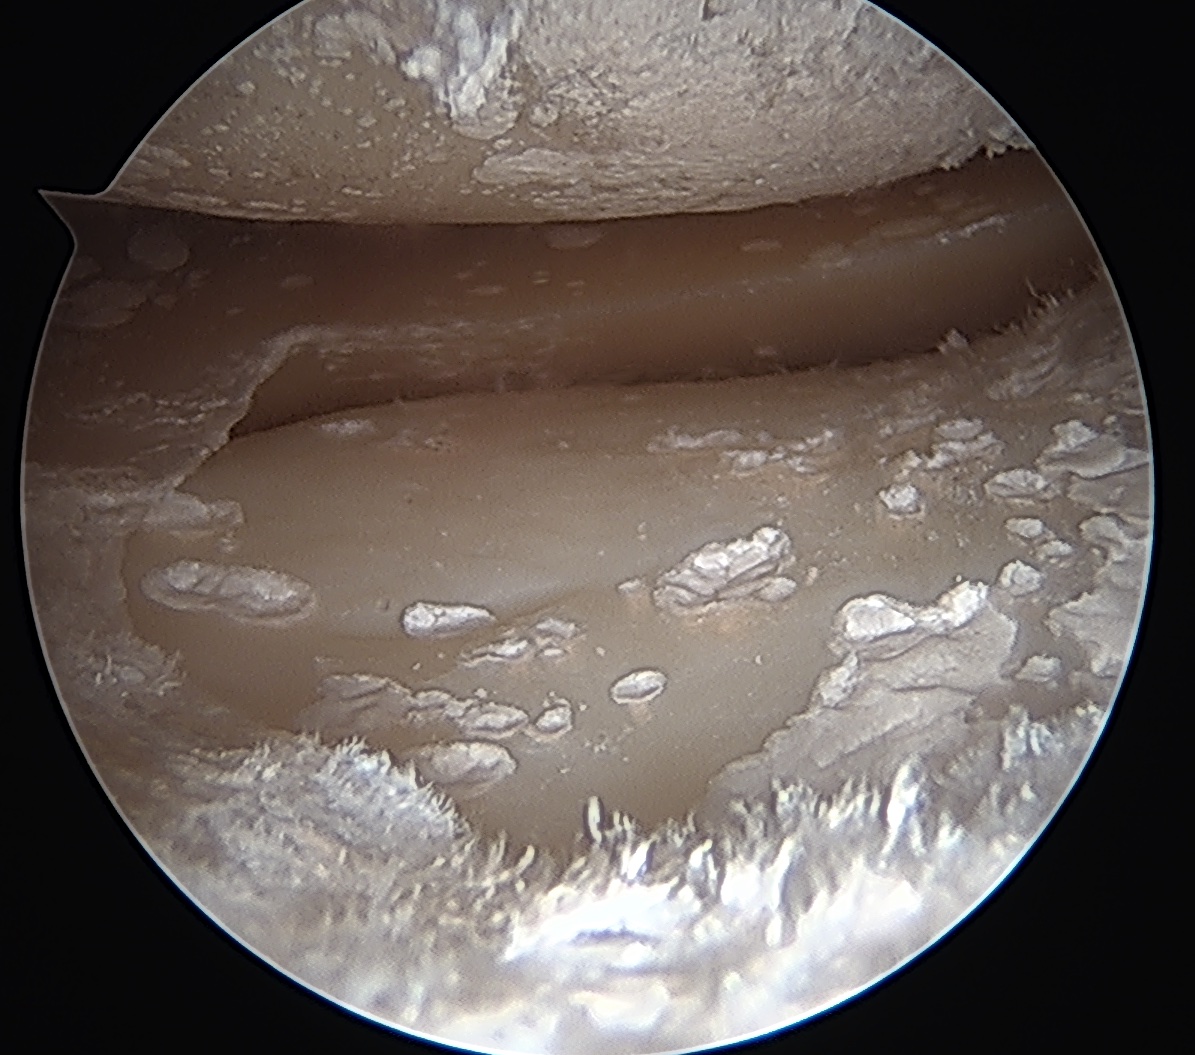

Arthroscopy